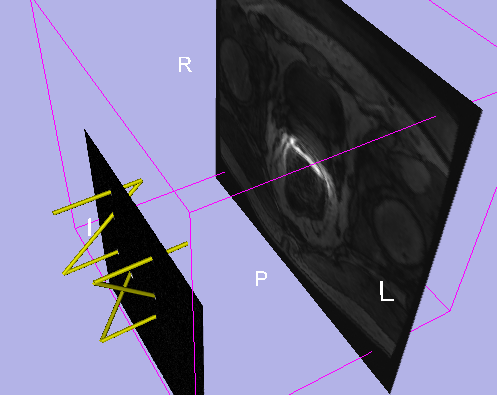

The software system consists of three sub-components: a) control software for the needle placement robot, b) software to control a closed-bore whole body 3T MRI scanner (GE Excite HD 3T, GE Healthcare), and c) open-source surgical navigation software (3D Slicer, http://www.slicer.org/). The core component of the software system is 3D Slicer, running on a Linux-based workstation, that serves as an integrated environment for calibration, surgical planning, image guidance and device monitoring and control. The 3D Slicer communicates with the other components through 100 Base-T Ethernet to exchange data and commands using an open network communication protocol, OpenIGTLink. We developed a software module in 3D Slicer that offers all features uniquely required for MR-guided robotic prostate intervention, as follows: 1) management of the ‘workphase’ of the all components in the system; 2) treatment planning by placing target points on the pre-operative 3D images loaded on the 3D Slicer and robot control based on the plan; 3) registration of the robot and patient coordinate systems; 4) integrated visualization of real-time 2D image, preoperative 3D image, and visualization of the current needle position on the 3D viewer of 3D Slicer.

During IGT Workshop in 2008 (Boston, December 2008), we successfully tested communication among the navigation software (3D Slicer / RadVision), robot control software, and 3T MRI at BWH. Since then, we have been working primarily on two tasks: improvement of the pneumatic mechanism at JHU and volunteer studies to analyze the workspace in the 3T MRI at BWH.